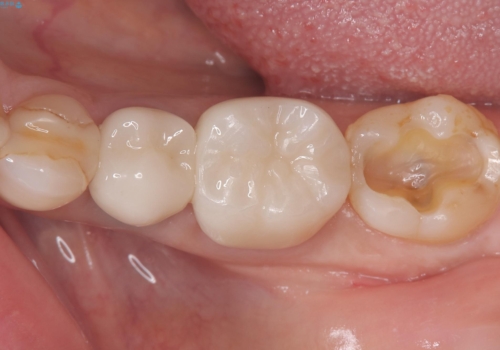

銀歯を白くしたい セラミックインレー

- 銀歯を白くしたいとのことでした。材料の違いを説明し、セラミックインレーでの治療となりました。

接着操作時にラバーダム防湿を行いました。